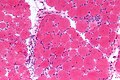

| H&E stain | routine, fibre size, shape, nuclei | H&E[15], H&E (WC) |

Features:

- Endomysial fibrosis.

- Hypercontracted fibres (large muscle fibres).